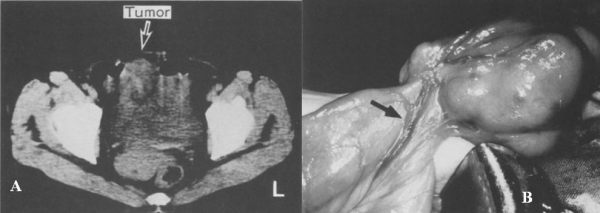

Hình 36: leiomyosarcoma ở bệnh nhân nữ 49 tuổi. A, CT thấy mass mô mềm tròn nằm bên phải tử cung. B, hình phẫu thuật, túi thừa Meckel với động mạch rốn ruột xuất phát từ mạc treo (mũi tên), có u nhú bên trong túi thừa. Giải phẫu bệnh : leiomyosarcoma. (Nobuyuki Shimizu, Shu Kuramoto et al (1997). Leiomyosarcoma Originating in Meckel’s Diverticulum: Report of a Case and a Review of 59 Cases in the English Literature. Surg Today 27:547)